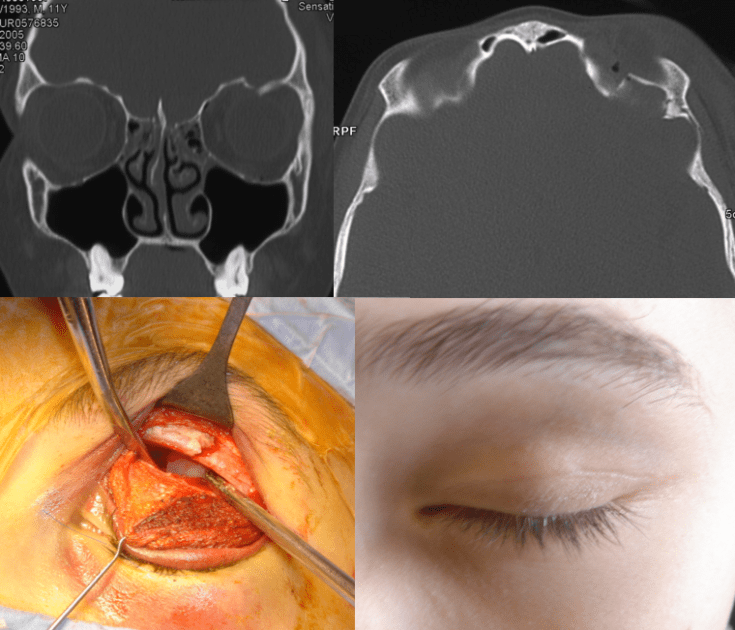

la reconstruction du toît d’orbite par voie palpébrale

- dans le pli palpébral parfois (Cf. ci-dessous)

- souvent de restaurer une morphologie harmonieuse en cas de déformation en région glabre (Cf. ci-contre)